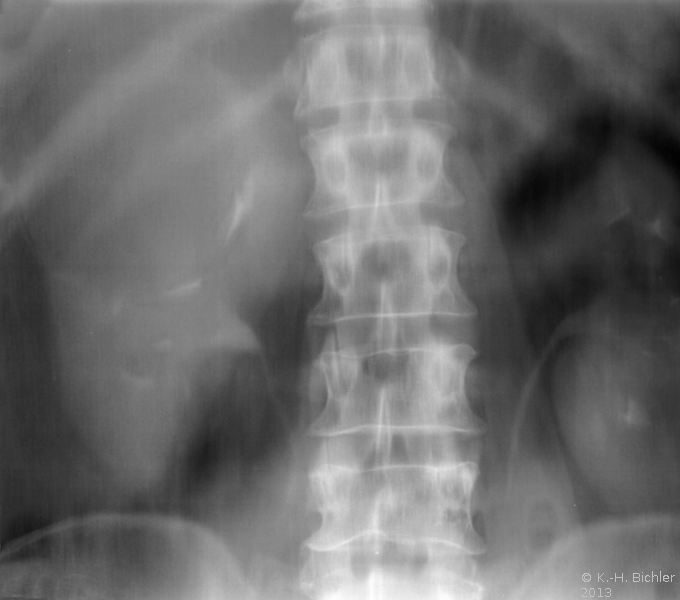

Diagnose und Behandlung von komplexen renalen Zysten bzw. unklaren Befunden umfassen eine Kombination von Sonographie, Urographie und CT (Abbildung 1). Dadurch soll eine Abgrenzung zwischen gutartigen und bösartigen Veränderungen erfolgen.